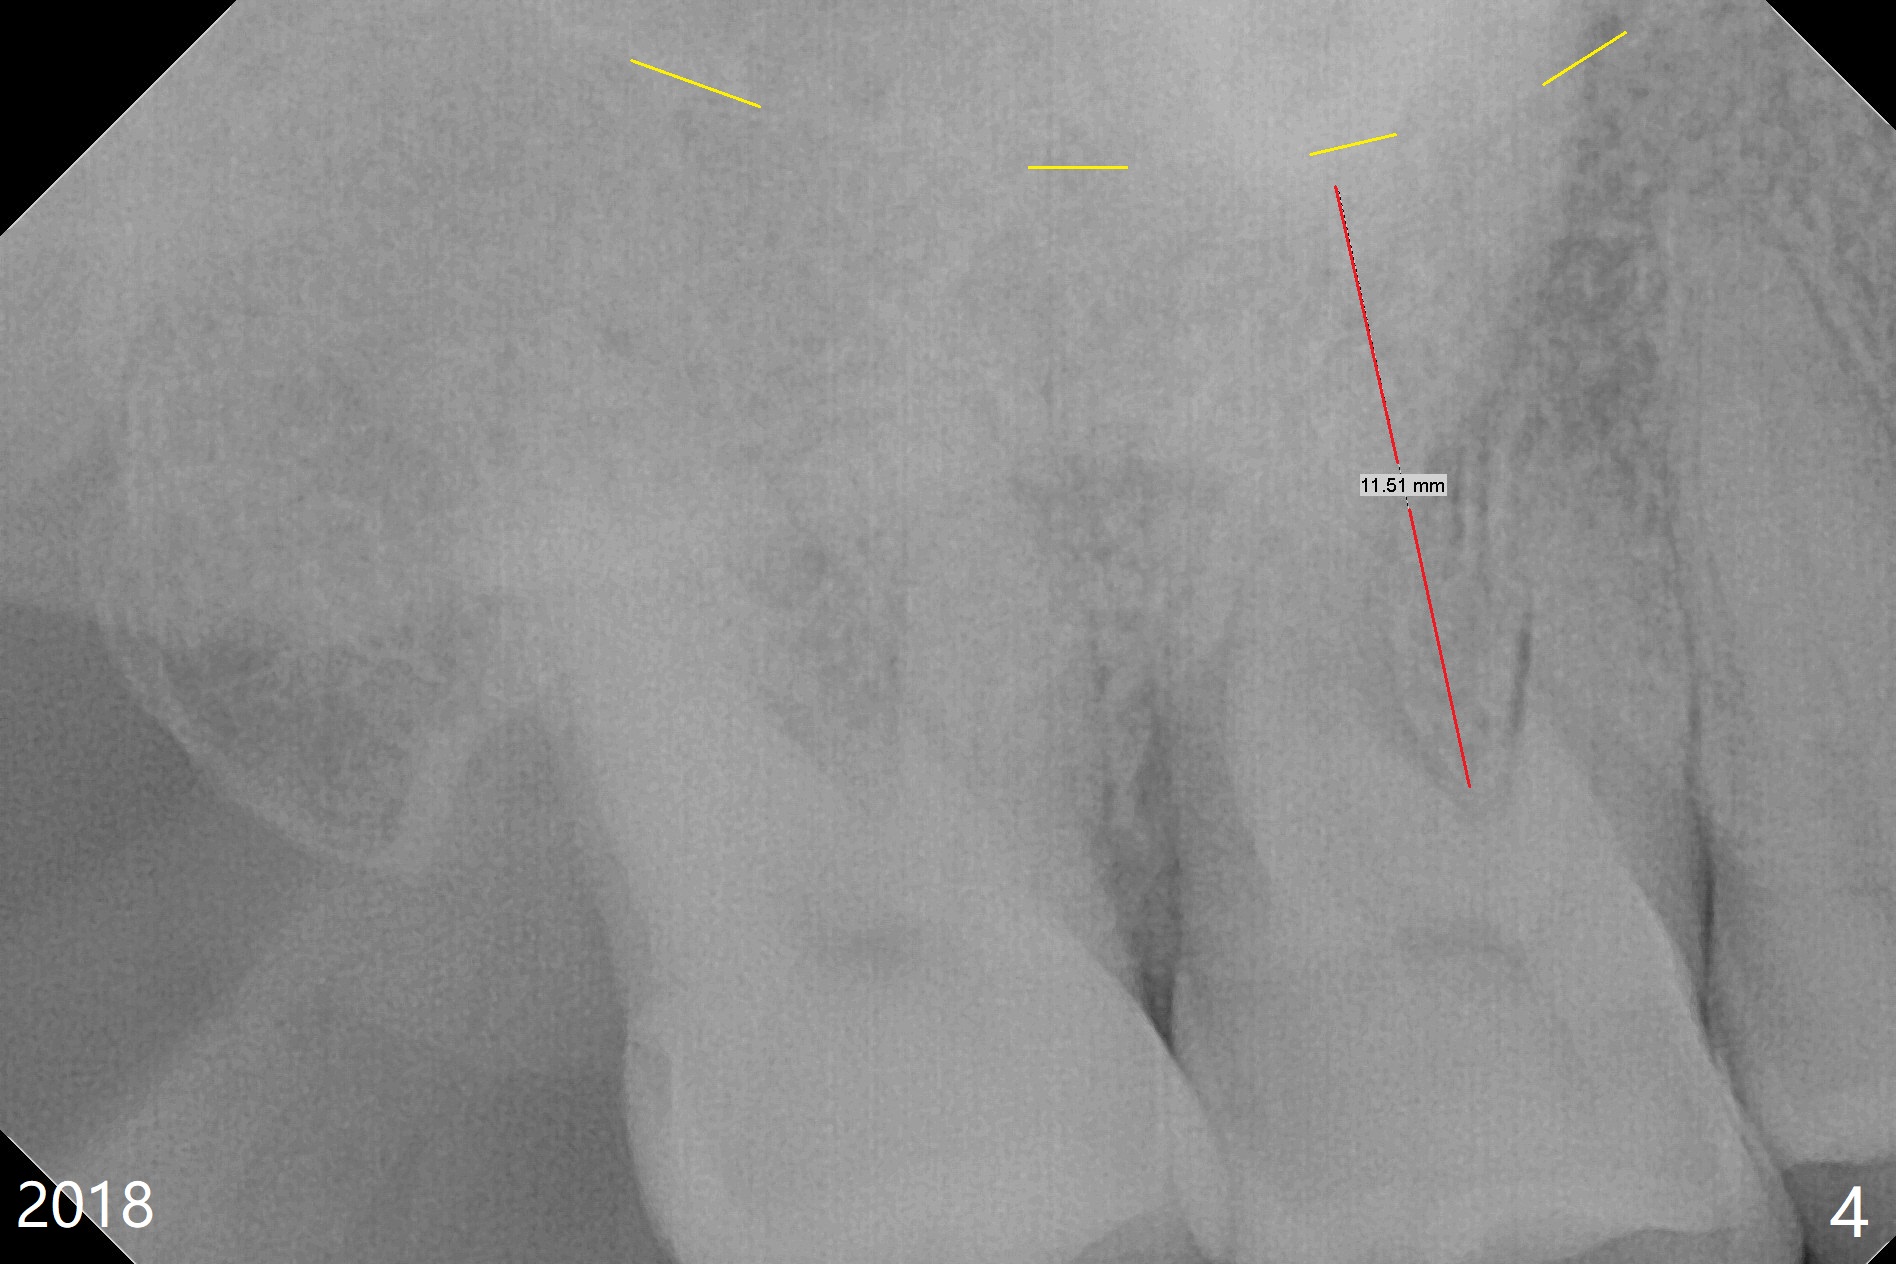

A 65-year-old woman has had signs & symptoms of crack tooth at #3 for the last 4 years (Fig.1-3). Finally the tooth is tender for mastication. Since the socket has infection and the bone is long (Fig.4 red line), an implant will be placed shy of the sinus floor (yellow dashed line). The bone loss (Fig.2,3 ^) may be associated with bruxism, which is detrimental to implant osteointegration. The immediate provisional should have enough occlusal clearance.